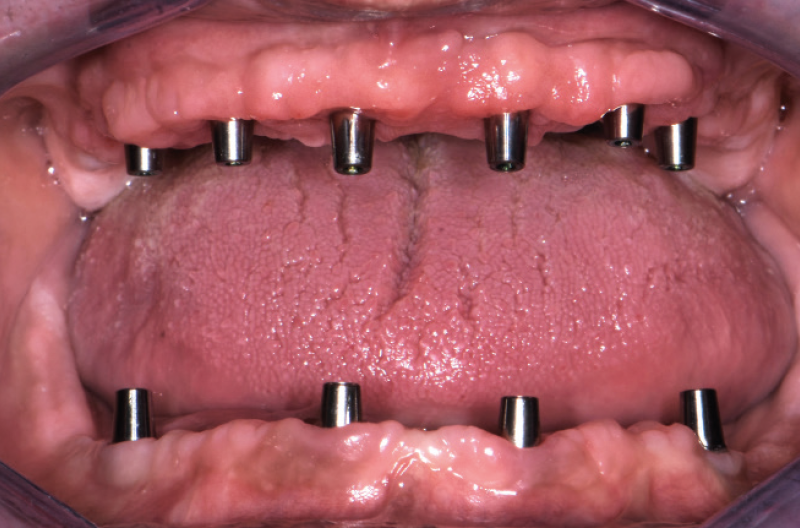

Nel mese di luglio 2019 il paziente ├© stato operato con il contestuale inserimento di 10 impianti, 4 nellŌĆÖarcata inferiore e 6 nellŌĆÖarcata superiore. Ho inserito 4 impianti Max Stability ├ś 3,75 mm nella zona della premaxilla, uno lungo 10 mm e gli altri tre da 12 mm di lunghezza; in regione 15 e 25 ho dovuto invece utilizzare delle frese da osseodensificazione per compattare lŌĆÖosso e traslare la parete mediale del seno mascellare per poter inserire 2 impianti Max Stability ├ś 3,75 L 12 mm inclinandoli lungo la parete stessa. Data la scarsa quantit├Ā e qualit├Ā di osso nel mascellare, ho rinunciato al carico immediato rinviando la procedura della protesizzazione immediata nella fase di riapertura degli impianti ad osteointegrazione avvenuta (Figg. 1-14).

NellŌĆÖarcata inferiore ho posizionato distalmente 2 impianti Max Stability ├ś 3,75 mm L 12 e L 14 mm inclinati (ŌĆ£tiltatiŌĆØ) davanti ai forami mentonieri secondo il protocollo All-on-four, mentre nella zona sinfisaria ho inserito 2 impianti Narrow ├ś 2,9 L 12 mm (Figg. 15-20).

Utilizzando i monconi di prova, sono stati scelti i monconi MUA pi├╣ idonei e prelevati dalla valigetta All-on-Four/All-on-Six messa a disposizione dalla Leone: due MUA GH 1,5 mm angolati a 7,5┬░ e due MUA GH 3 mm angolati a 35┬░. Una volta posizionati negli impianti non mi restava che parallelizzarli, operazione resa facile dalla vite blu polifunzionale gi├Ā premontata e dalla possibilit├Ā di ruotare i monconi a 360┬░ (Figg. 21,22).

Fig. 21 – Visualizzazione dellŌĆÖinclinazione degli impianti